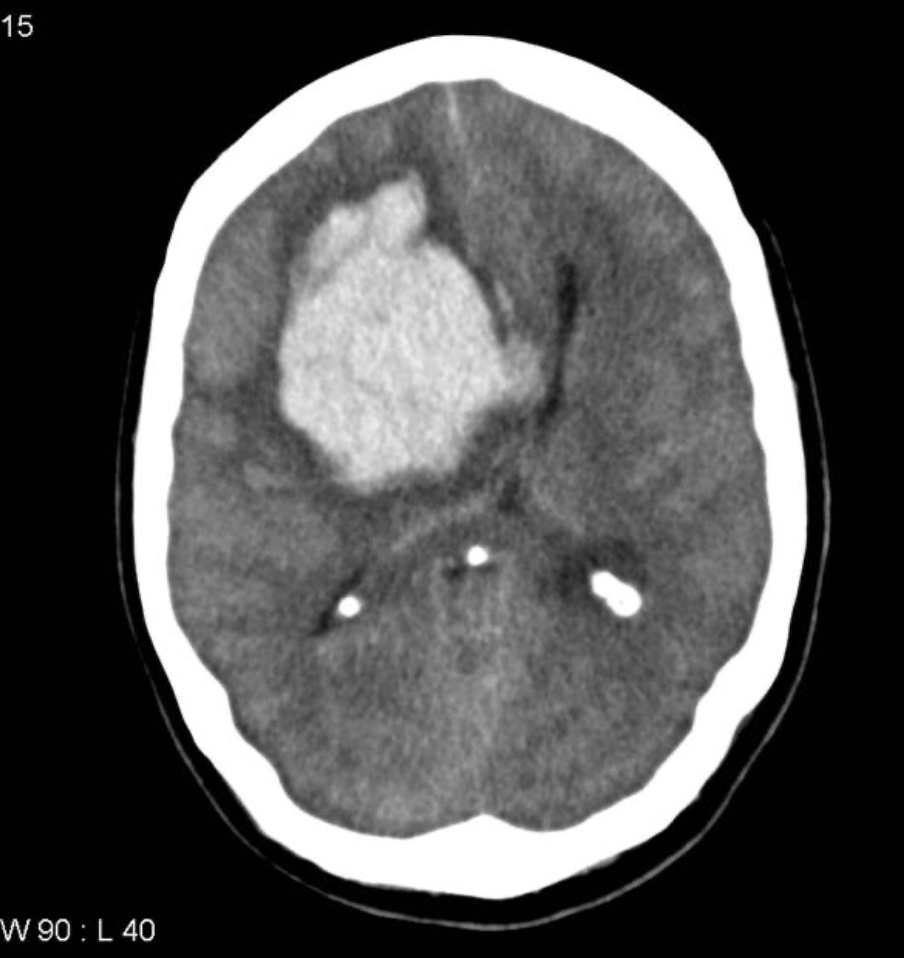

Hemorraagiline insult KT-uuringul

Kompuutertomograafia peaajust natiivis – tehakse kõigile insuldikahtlusega patsientidel, on võimalik eristada, kas tegemist on isheemilise või hemorraagilise insuldiga.

- intratserebraalne hemorraagia – verejooks lähtub arterioolidest või väikestest arteritest. Verejooks põhjustab peaajusisese lokaalse hematoomi, mis suureneb minutite või tundide jooksul. Enamasti põhjustatud hüpertensioonist, amüloidangiopaatiast või verevedeldajate kasutamisest.